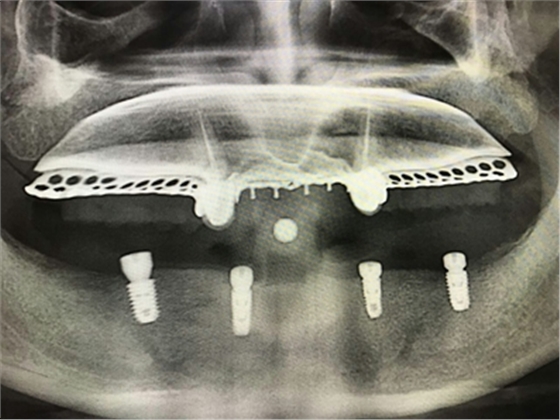

毛國(guó)斌種植病例——群討論分享